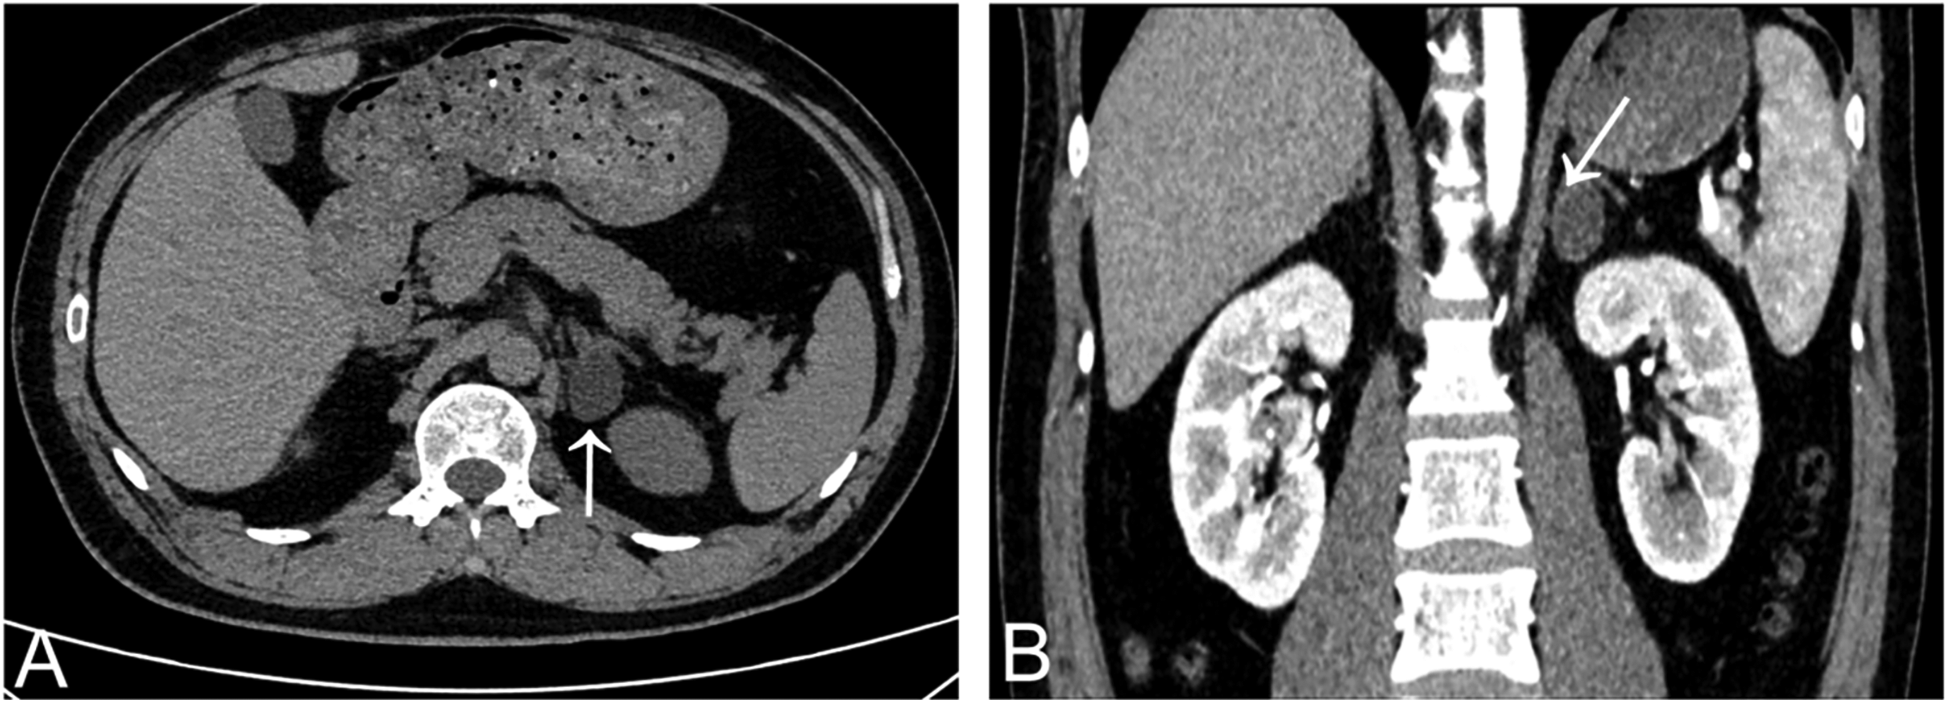

A 37-year-old man diagnosed with hypertension for 3 years was referred to the cardiology department for evaluation of possible secondary hypertension. He denied prior cerebrovascular accidents or cardiovascular diseases. Anthropometric measurements revealed a height of 175 cm and weight of 74 kg, yielding a body mass index (BMI) of 24.16 kg/m2. His peak recorded blood pressure (BP) was 185/130 mmHg. Despite daily therapy with nifedipine extended-release tablets 30 mg and sacubitril/valsartan 200 mg, BP control remained suboptimal: office BP was 160/110 mmHg, while 24 h ambulatory BP monitoring showed an average of 134/85 mmHg (daytime: 140/93 mmHg; nighttime: 124/73 mmHg). Laboratory findings were as follows (Table 1): hemoglobin 156 g/L, white blood cell count 10.07 × 109/L, platelet count 243 × 109/L; serum potassium 3.26 mmol/L, sodium 142.7 mmol/L, calcium 2.36 mmol/L; alanine aminotransferase (ALT) 60 U/L, aspartate aminotransferase (AST) 28 U/L; uric acid 455 μmol/L, triglycerides 1.96 mmol/L, total cholesterol 5.31 mmol/L, low-density lipoprotein cholesterol 3.73 mmol/L, and fasting blood glucose 4.95 mmol/L; creatinine 104.1 μmol/L, estimated glomerular filtration rate (eGFR) 80.22 ml/min/1.73 m2. Routine urinalysis revealed no abnormalities (negative for protein, glucose, ketones, and leukocytes). To avoid interference with aldosterone-to-renin ratio (ARR) assays, antihypertensive therapy was switched to doxazosin 8 mg daily and verapamil 240 mg daily over a one-month period. Direct renin concentration and aldosterone levels were measured using a chemiluminescent immunoassay platform at our center. Hormonal evaluation in the upright position revealed: plasma aldosterone concentration (PAC) 937.18 pmol/L, suppressed renin 1.60 pg/ml, and ARR 585.74. In the supine position, results showed: PAC > 1,000 pmol/L, suppressed renin 1.71 pg/ml, and incalculable ARR due to unmeasurably high aldosterone levels. Circadian rhythm of serum cortisol and adrenocorticotropic hormone, plasma free metanephrines, and thyroid function were within normal range. The combination of markedly elevated aldosterone and suppressed renin suggested probable primary aldosteronism (PA). A supine saline suppression test was subsequently performed, involving intravenous infusion of 2 L of 0.9% sodium chloride solution over 4 h, with blood samples collected at baseline and post-infusion. Results demonstrated: baseline PAC > 1,000 pmol/L, renin 1.28 pg/ml; Post-infusion PAC > 1,000 pmol/L, renin 1.04 pg/ml. These findings confirmed autonomous aldosterone excess, supporting a PA diagnosis. Contrast-enhanced adrenal computed tomography (CT) scan identified a 1 cm left adrenal nodule with an attenuation value of 1 Hounsfield unit (HU), consistent with a lipid-rich adenoma (Figure 2).

Figure 2. Adrenal gland CT scan showed a lipid-rich left adrenal nodule (arrows) [(A) non-contrast enhanced CT; (B) contrast-enhanced CT].

The patient was transferred to the coronary care unit postoperatively and received continuous electrocardiographic monitoring until postoperative day 3. Post-intervention hematological parameters and clinical data were summarized in Table 1. Post-intervention assessments demonstrated a gradual normalization of the aldosterone-to-renin ratio (ARR), and blood pressure progressively declined and ultimately stabilized within the normal range. On postoperative day 1 (POD1), a significant decrease in aldosterone levels (PAC = 175.29 pg/ml) was noted. However, renin suppression persisted (renin = 1.14 pg/ml) and ARR still elevated (ARR = 93.97). By POD2, aldosterone concentrations further declined to near-physiological ranges (PAC = 80.61 pg/ml), while renin-aldosterone axis dysfunction persisted (renin = 1.14 pg/ml, ARR = 70.71). Notably, physiological equilibrium was restored by POD3, characterized by complete resolution of renin suppression (renin = 3.74 pg/ml), sustained decrease in aldosterone concentrations (PAC = 68.00 pg/ml) and ARR normalization (ARR = 18.18), indicating restored negative feedback mechanisms. The patient was discharged on POD 3. At the 1-month follow-up, serum potassium concentration remained within normal range (4.2 mmol/L; reference: 3.5–5.0 mmol/L) without potassium supplementation. Both clinic blood pressure (132/82 mmHg) and 24 h average blood pressure (124/71 mmHg) were maintained within acceptable limits off antihypertensive therapy. Concurrent aldosterone-renin ratio testing revealed persistently low serum aldosterone (PAC = 78.25 pg/ml) alongside complete reversal of prior renin suppression (renin = 4.52 pg/ml). These results indicated that the patient achieved complete biochemical success and clinical cure of hypertension during the observation period, according to the PASO criteria (16).